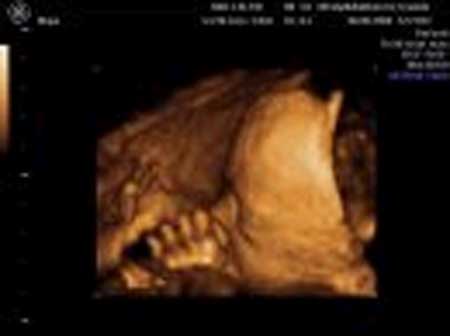

3D scanning – se baby i maven under graviditeten

3d scanning uge 26

3d scanning – uge 26